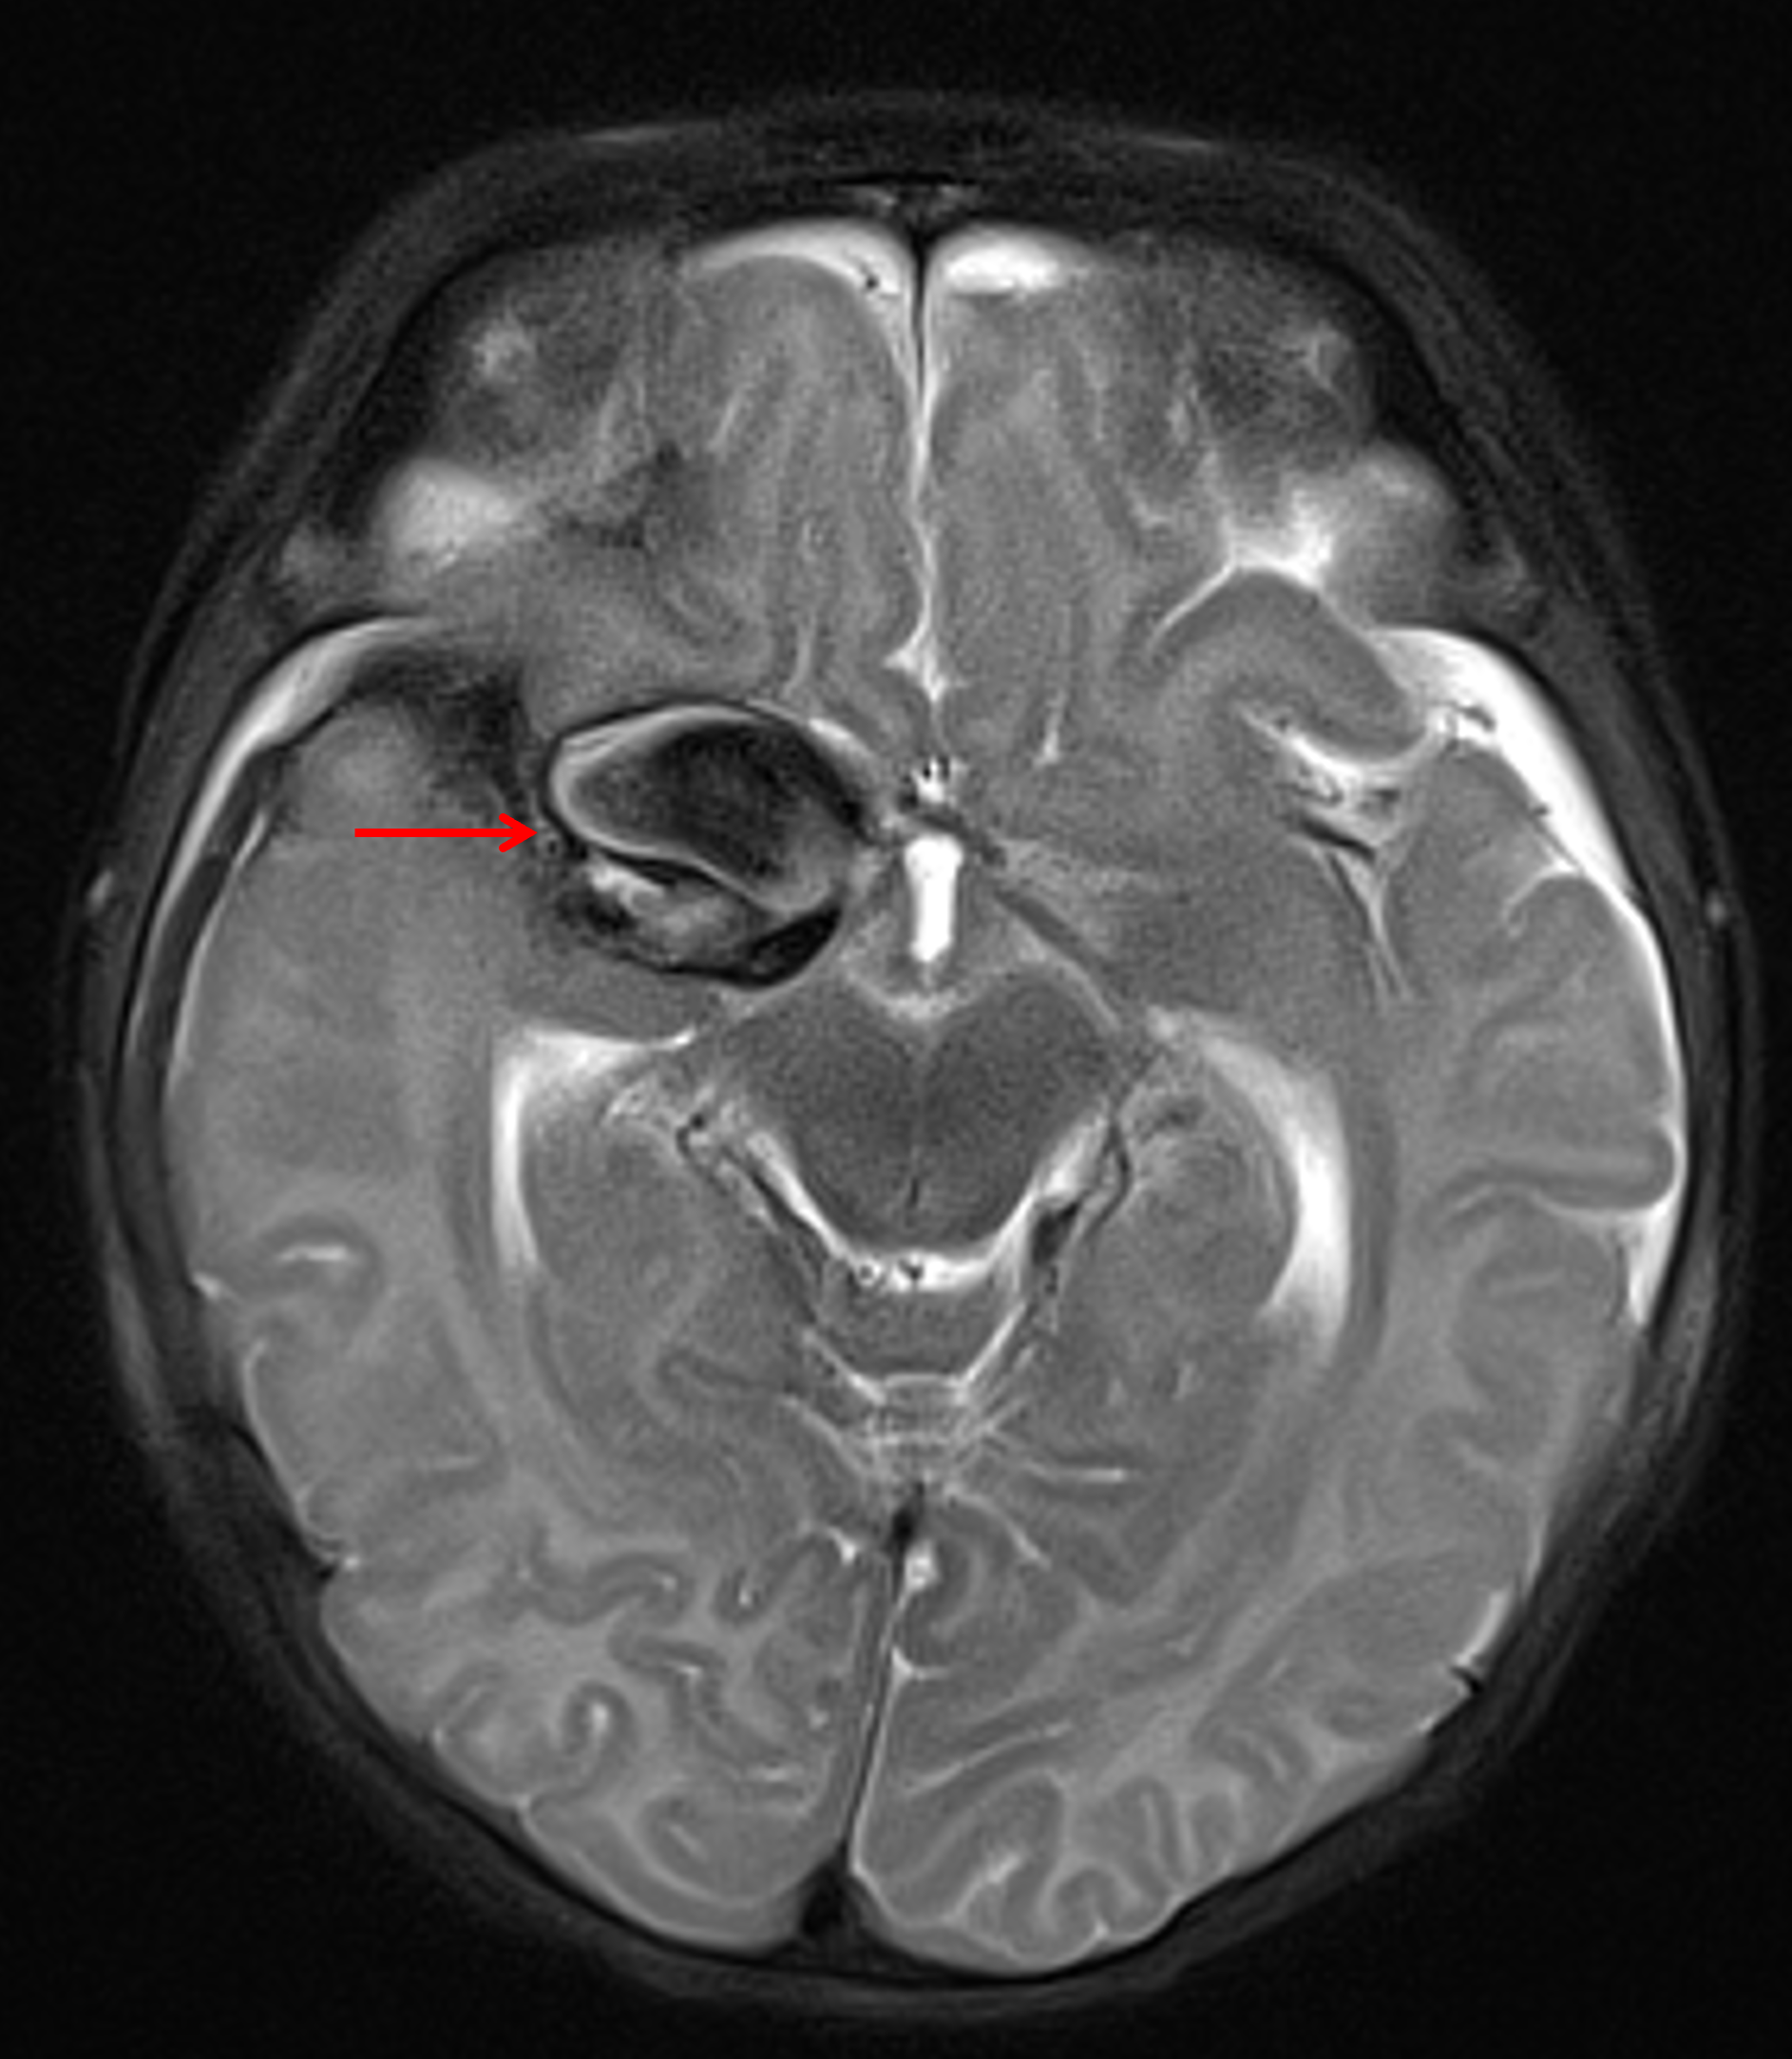

Age: 2 months

Sex: Female

Indication: Fussiness, bulging anterior fontanelle

MRI

Giant cerebral aneurysm